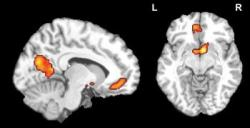

"Nie je to síce celkom jasná predpoveď hitu, avšak v údajoch sme predsa len našli štatisticky významnú súvislosť," povedal Gregory Berns. Sám vzorku dobrovoľníkov nepovažuje v danom kontexte za úplne reprezentatívnu. Jednak kvôli pomerne nízkemu počtu subjektov, jednak kvôli faktu, že to boli tínedžeri – a tí tvoria iba asi pätinu ľudí, ktorí si kupujú hudbu. Väčšina skúmaných pesničiek zostala neúspešná, čo jasne ukázali už mozgové reakcie tínedžerov. Iba tri postupne splnili kritériá pre hit, teda predaj najmenej 500.000 kópií v rámci albumov, alebo jednotlivých digitálnych stiahnutí cez internet. Z mozgových reakcií tínedžerov, prevažne v oblastiach označovaných ako cuneus, orbitofrontálna kôra a ventrálne striatum (centrá odmien), sa však dalo odvodiť aj to, ktoré pesničky napokon prekročili predaj 20.000 kópií – bola to približne tretina.